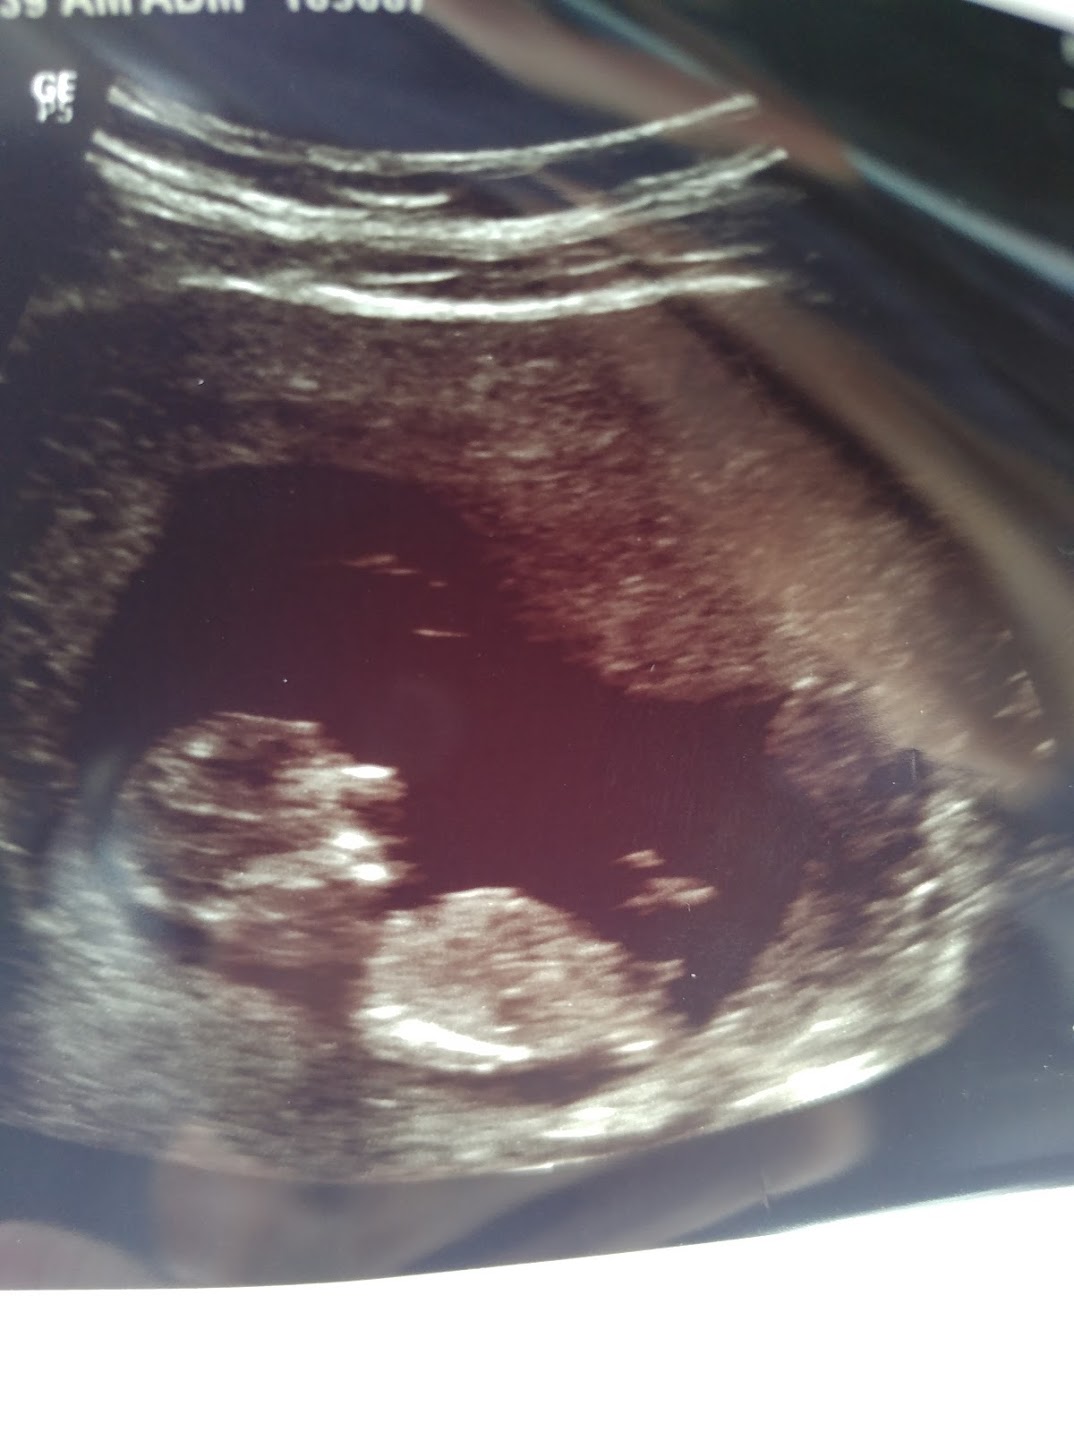

I also posted in the private but it looks like less traffic there. I would REALLY appreciate guesses. We did a VERY strict sway for 3 months, and I find out Friday morning. Ramzi is 8w3d transvaginal and nub is 12w3d abdominal. Thank you so much for guessing!!!!! I'll be sure to update.Attachment 41231Attachment 41232